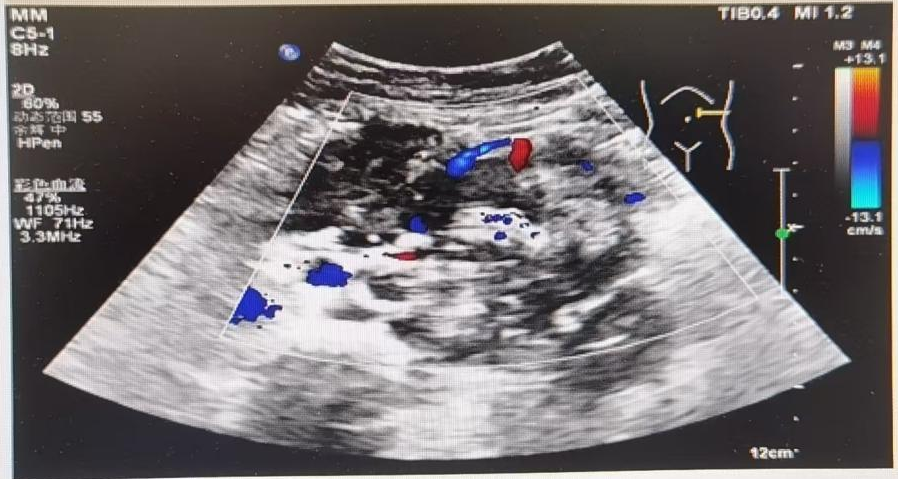

B超(2022.5.17)

▪ 左中上腹实性肿物——考虑恶性,神经母细胞瘤可能性大,大小约12.3×9.9×6.5cm。

▪ 腹膜后多发淋巴结肿大——考虑转移瘤,最大5.1×2.9×2.4cm。

▪ 左颈部多发实性肿物——考虑转移瘤,最大3.8×2.2×1.8cm。